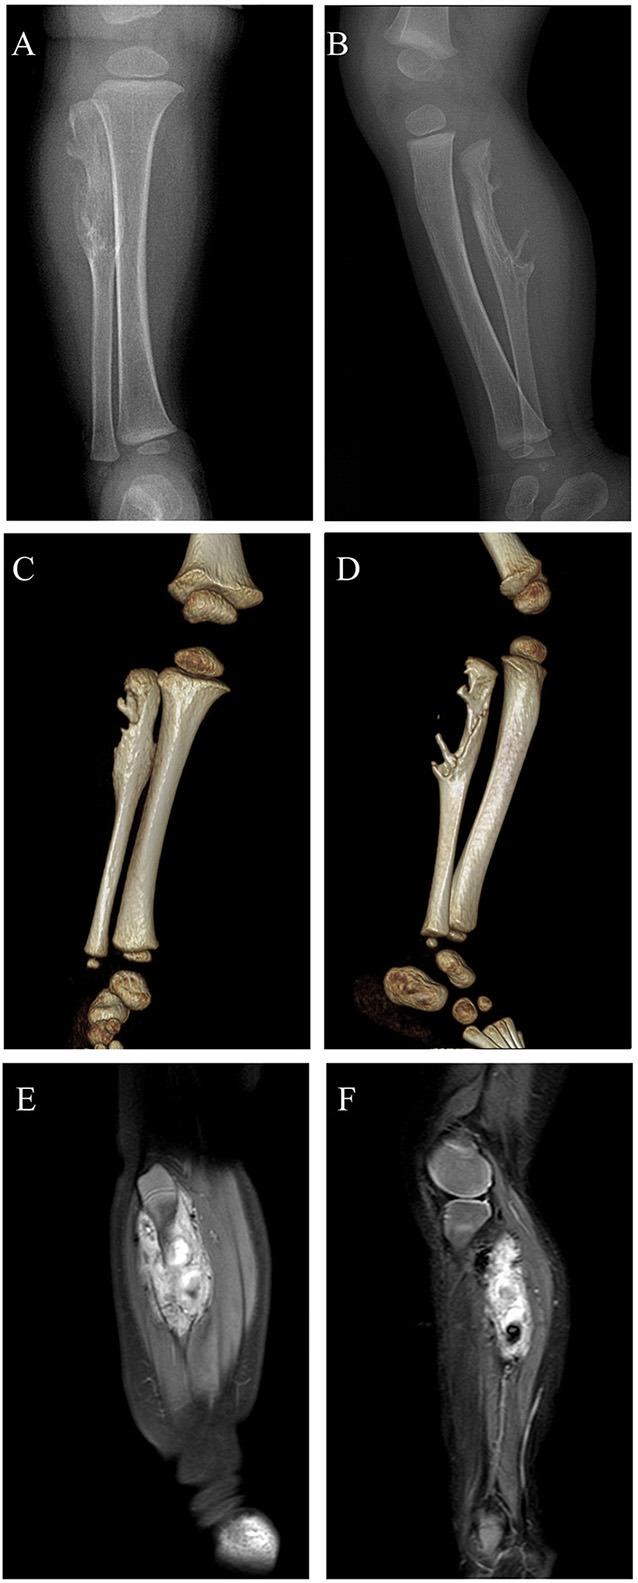

Spindle cell hemangioma (SCH), a non-neoplastic reactive vascular lesion, rarely locates in bones. We herein report a successful case of intralesional curettage for an infant with SCH of fibula. An 11-month-old boy was admitted to our center with a painless mass in the right proximal calf. Preoperative digital radiograph demonstrated a massive vascular lesion with an irregular bone destruction of proximal fibula. The lesion was removed via the intralesional curettage approach and pathologically diagnosed as SCH. The patient gained bone structure recovery of right proximal fibula. Two years after the surgery, he experienced no local recurrence. For the management of SCH of fibula with partial bone destruction, we suggest early-stage intralesional curettage as its safety and effectiveness.

摘要